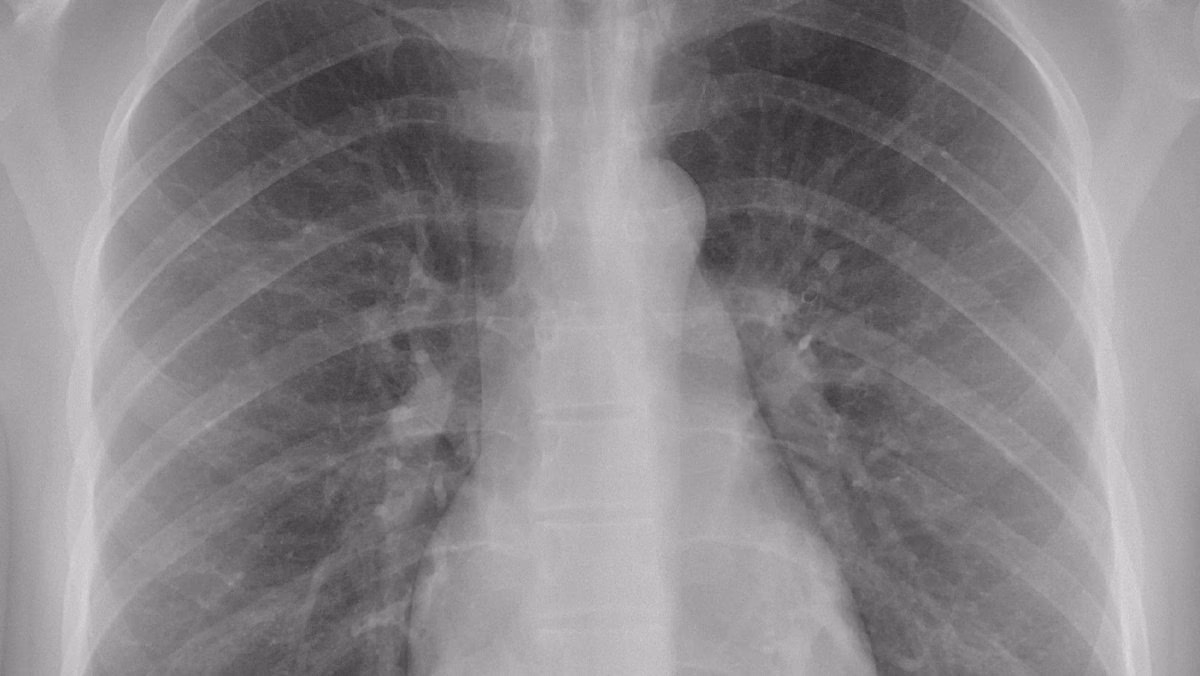

Paradoksalt nok er den samme teknologi, der bærer en minimal risiko, et af vores mest kraftfulde værktøjer til at opdage kræft. Røntgenbilleddannelse fungerer ved at sende elektromagnetiske stråler gennem kroppen. Forskellige væv absorberer disse stråler i forskellig grad. Tæt væv som knogler absorberer meget stråling og fremstår hvidt på billedet, mens blødere væv som lunger lader mere stråling passere og fremstår mørkere. Kræftknuder har ofte en anden tæthed end det omgivende sunde væv, hvilket kan få dem til at fremstå som unormale skygger eller masser på et røntgenbillede.

- Unormale masser eller knuder: En af de mest almindelige indikationer, især ved lungekræft, hvor en tumor kan ses som en lys plet i det ellers mørke lungevæv.

Det er dog afgørende at forstå, at et røntgenbillede sjældent giver en endelig diagnose alene. Mange godartede tilstande, såsom arvæv, cyster eller infektioner, kan ligne kræft på et røntgenbillede. Derfor er et mistænkeligt fund på et røntgenbillede typisk det første skridt i en længere diagnostisk proces.